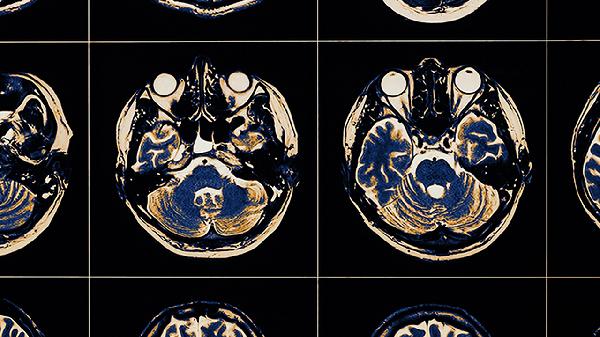

孕中期通过超声系统筛查可测量胎儿头围与双顶径,头围低于同孕周平均值3个标准差需警惕。核磁共振能更清晰显示脑部结构异常,如脑回发育不良、胼胝体缺失等。发现异常时应每2-4周复查动态监测生长趋势。